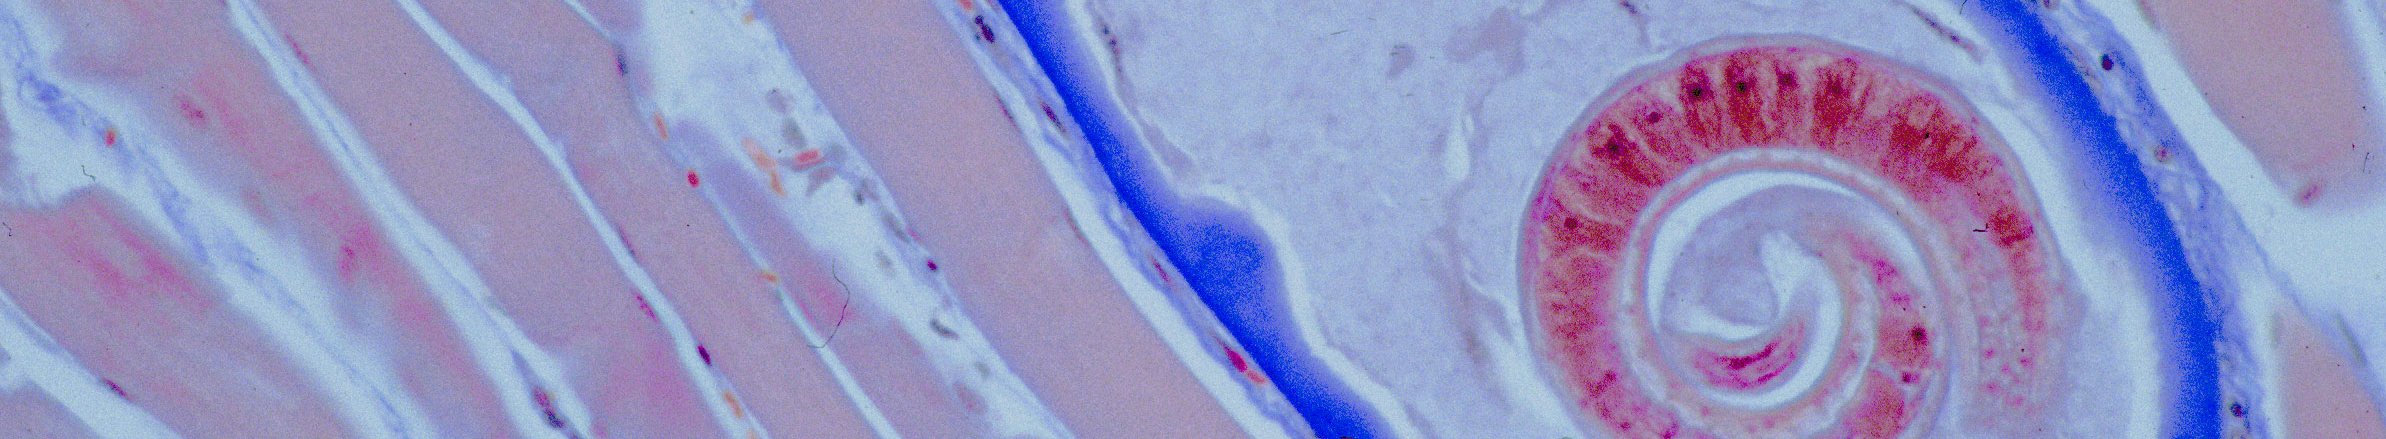

Besondere Bedeutung für den Menschen haben die Trichinellen, auch als Trichinen bezeichnet, das sind Darmwürmer, deren Larven sich in der Muskulatur als sehr unempfindliche Dauerstadien einnisten. Diese sind mit bloßem Auge nur dann erkennbar, wenn sie in großer Menge vorhanden und verkalkt sind. Die Befallsrate ist bei Wildschweinen häufiger als beim Hausschwein. Der Verzehr rohen beziehungsweise nicht durchgegarten trichinösen Schweinefleisches führt zu rheumaartigen Beschwerden, die mit dem Tod des Patienten enden können.